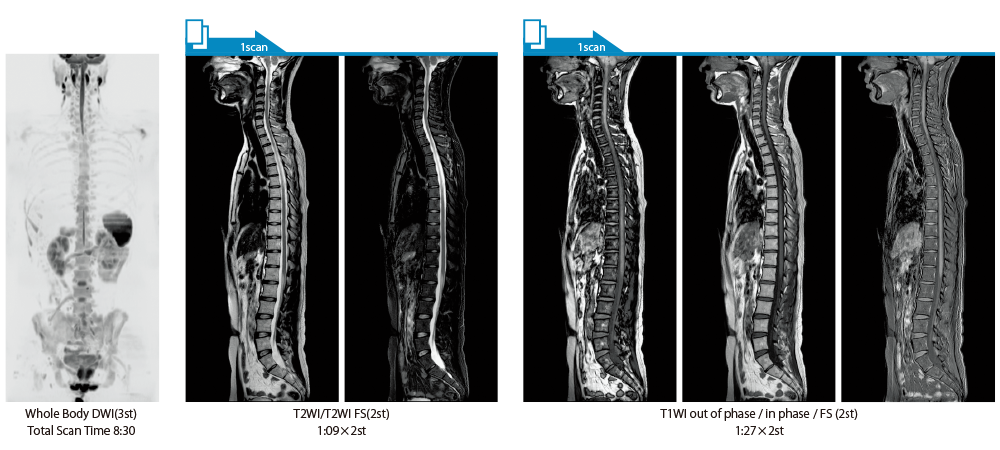

It can also be used with time-consuming scans such as Whole Body DWI and Whole Spine imaging, providing more detailed information in many areas than previously possible.